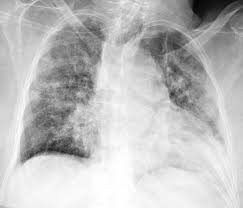

1. Foto polos : digunakan untuk melihat adanya infeksi di paru dan status pulmoner